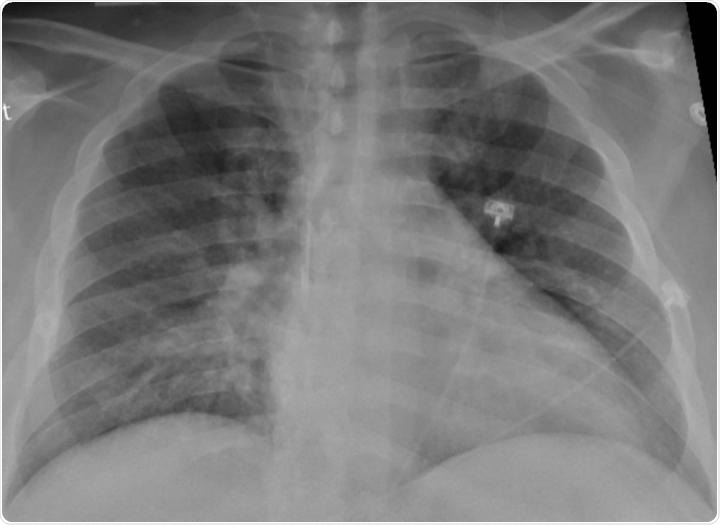

While much is known about the respiratory impact of COVID-19 infection, given that the virus’s primary target is the respiratory system. With COVID-19 inducing inflammation of the lungs, people who contract the infection face an increased risk of developing pneumonia. For this reason, those with current or prior respiratory illness or complications are often given tailored advice from their healthcare agency. Often, this group of people is considered to be at-risk and is encouraged to uphold stricter measures to afford them increased protection from contracting the virus.

Image Credit: Andrii Vodolazhskyi/Shutterstock.com